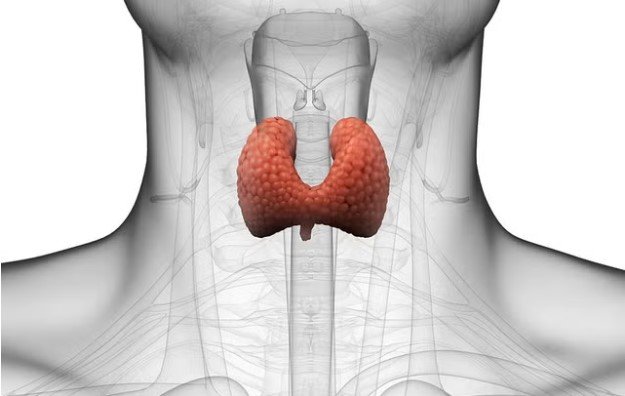

How Symptoms Of Thyroid Deficiency Differ In Men And Women

Thyroid health plays a crucial role in regulating metabolism, energy levels, and overall well-being. When the thyroid gland fails to produce sufficient hormones, it can lead to a range of health issues that impact both men and women. Understanding the symptoms of thyroid deficiency is essential for early detection and effective management. While some signs are common across genders, the manifestation of these symptoms often differs between men and women due to hormonal variations and physiological differences. Recognizing these distinctions can help individuals seek timely medical care and improve their quality of life.